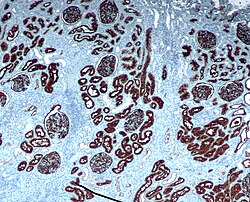

CD10 staining in normal kidney.